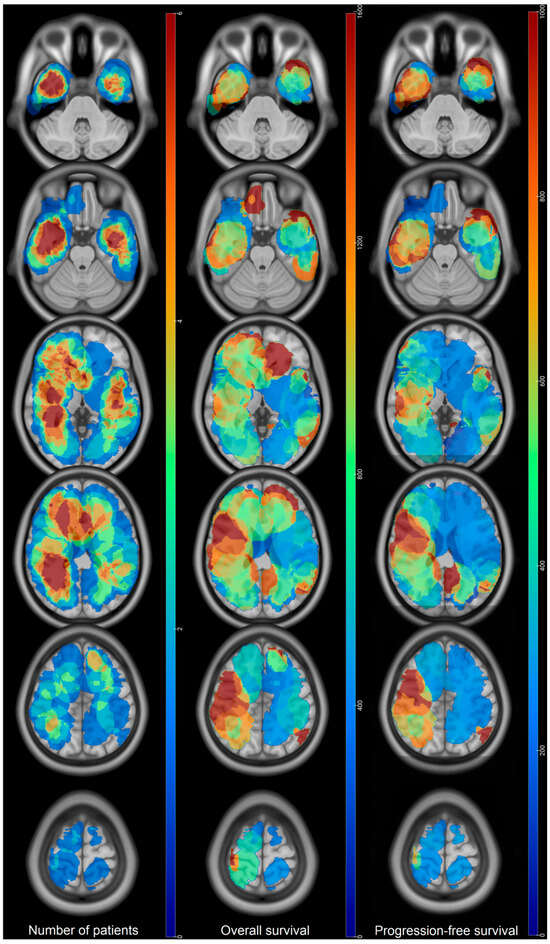

Prognostic Factors of IDH Wild-Type Glioblastoma After Extensive Surgery: A Multimodal Atlas of Tumor Locations, Recurrences and Management

by Hajar Selhane, Tiphaine Obara, Guillaume Vogin, René Anxionnat, Guillaume Gauchotte, Luc Taillandier, Marie Blonski and Fabien Rech

Cancers 2026, 18(1), 63; https://doi.org/10.3390/cancers18010063 - 24 Dec 2025

Introduction: Glioblastomas have poor prognosis despite aggressive treatment. Patterns of recurrence and overall survival (OS) can be very different. The population with complete resection having a so-called good prognosis can nevertheless present poor OS. Our purpose was to assess the OS and patterns [...] Read more.

Introduction: Glioblastomas have poor prognosis despite aggressive treatment. Patterns of recurrence and overall survival (OS) can be very different. The population with complete resection having a so-called good prognosis can nevertheless present poor OS. Our purpose was to assess the OS and patterns of recurrence thanks to multimodal statistical maps in glioblastoma with large extent of resection (residue < 10 mL). Methods: adult patients presenting IDH wild-type glioblastoma between 2013 and 2019 were selected. Clinical data and MRI characteristics were collected. Preoperative, postoperative, and recurrence volumes were segmented and normalized in the MNI space to compute statistical maps. Log-rank test and Cox model were used to assess OS and prognosis factors. Results: 60 patients were included. Mean residual volume was 0.89 ± 2 mL. Median OS was 22.3 months (95% CI: (20–35)). Initial location in the corpus callosum was associated with low OS (317 vs. 783 days, HR = 0.46, p = 0.003). At recurrence, KPS > 90 and tumor volume < 10 mL were associated with higher OS (p =0.006 and p = 0.05). Tumor contact with the SVZ as well as multifocal recurrence did not show any impact on the OS. Conclusions: High OS can be obtained thanks to surgery with residual volume < 10 mL. Invasion of the corpus callosum at diagnosis is associated with a poor prognosis despite a large extent of resection. Results suggest that large resection near the SVZ might decrease its putative influence on OS. Full article

Figure 1